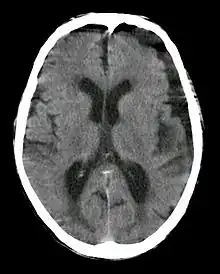

| Subdural hygroma, frontal and temporal. Man of 80 years old. | |

A subdural hygroma (SDG) is a collection of cerebrospinal fluid (CSF), without blood, located under the dural membrane of the brain. Most subdural hygromas are believed to be derived from chronic subdural hematomas. They are commonly seen in elderly people after minor trauma, but can also be seen in children following infection or trauma. One of the common causes of subdural hygroma is a sudden decrease in pressure as a result of placing a ventricular shunt. This can lead to leakage of CSF into the subdural space especially in cases with moderate to severe brain atrophy. In these cases, symptoms such as mild fever, headache, drowsiness and confusion can be seen, which can be relieved by draining this subdural fluid.

In CT scan, subdural hygroma will have same density as the normal CSF. Meanwhile, in MRI, subdural hygroma will have same intensity with CSF. If iodinated contrast is administered during CT scan, the hygroma will produce high density because of the contrast at 120 kVp. However, at 190 kVp, hygroma with contrast will have intermediate density.[2]